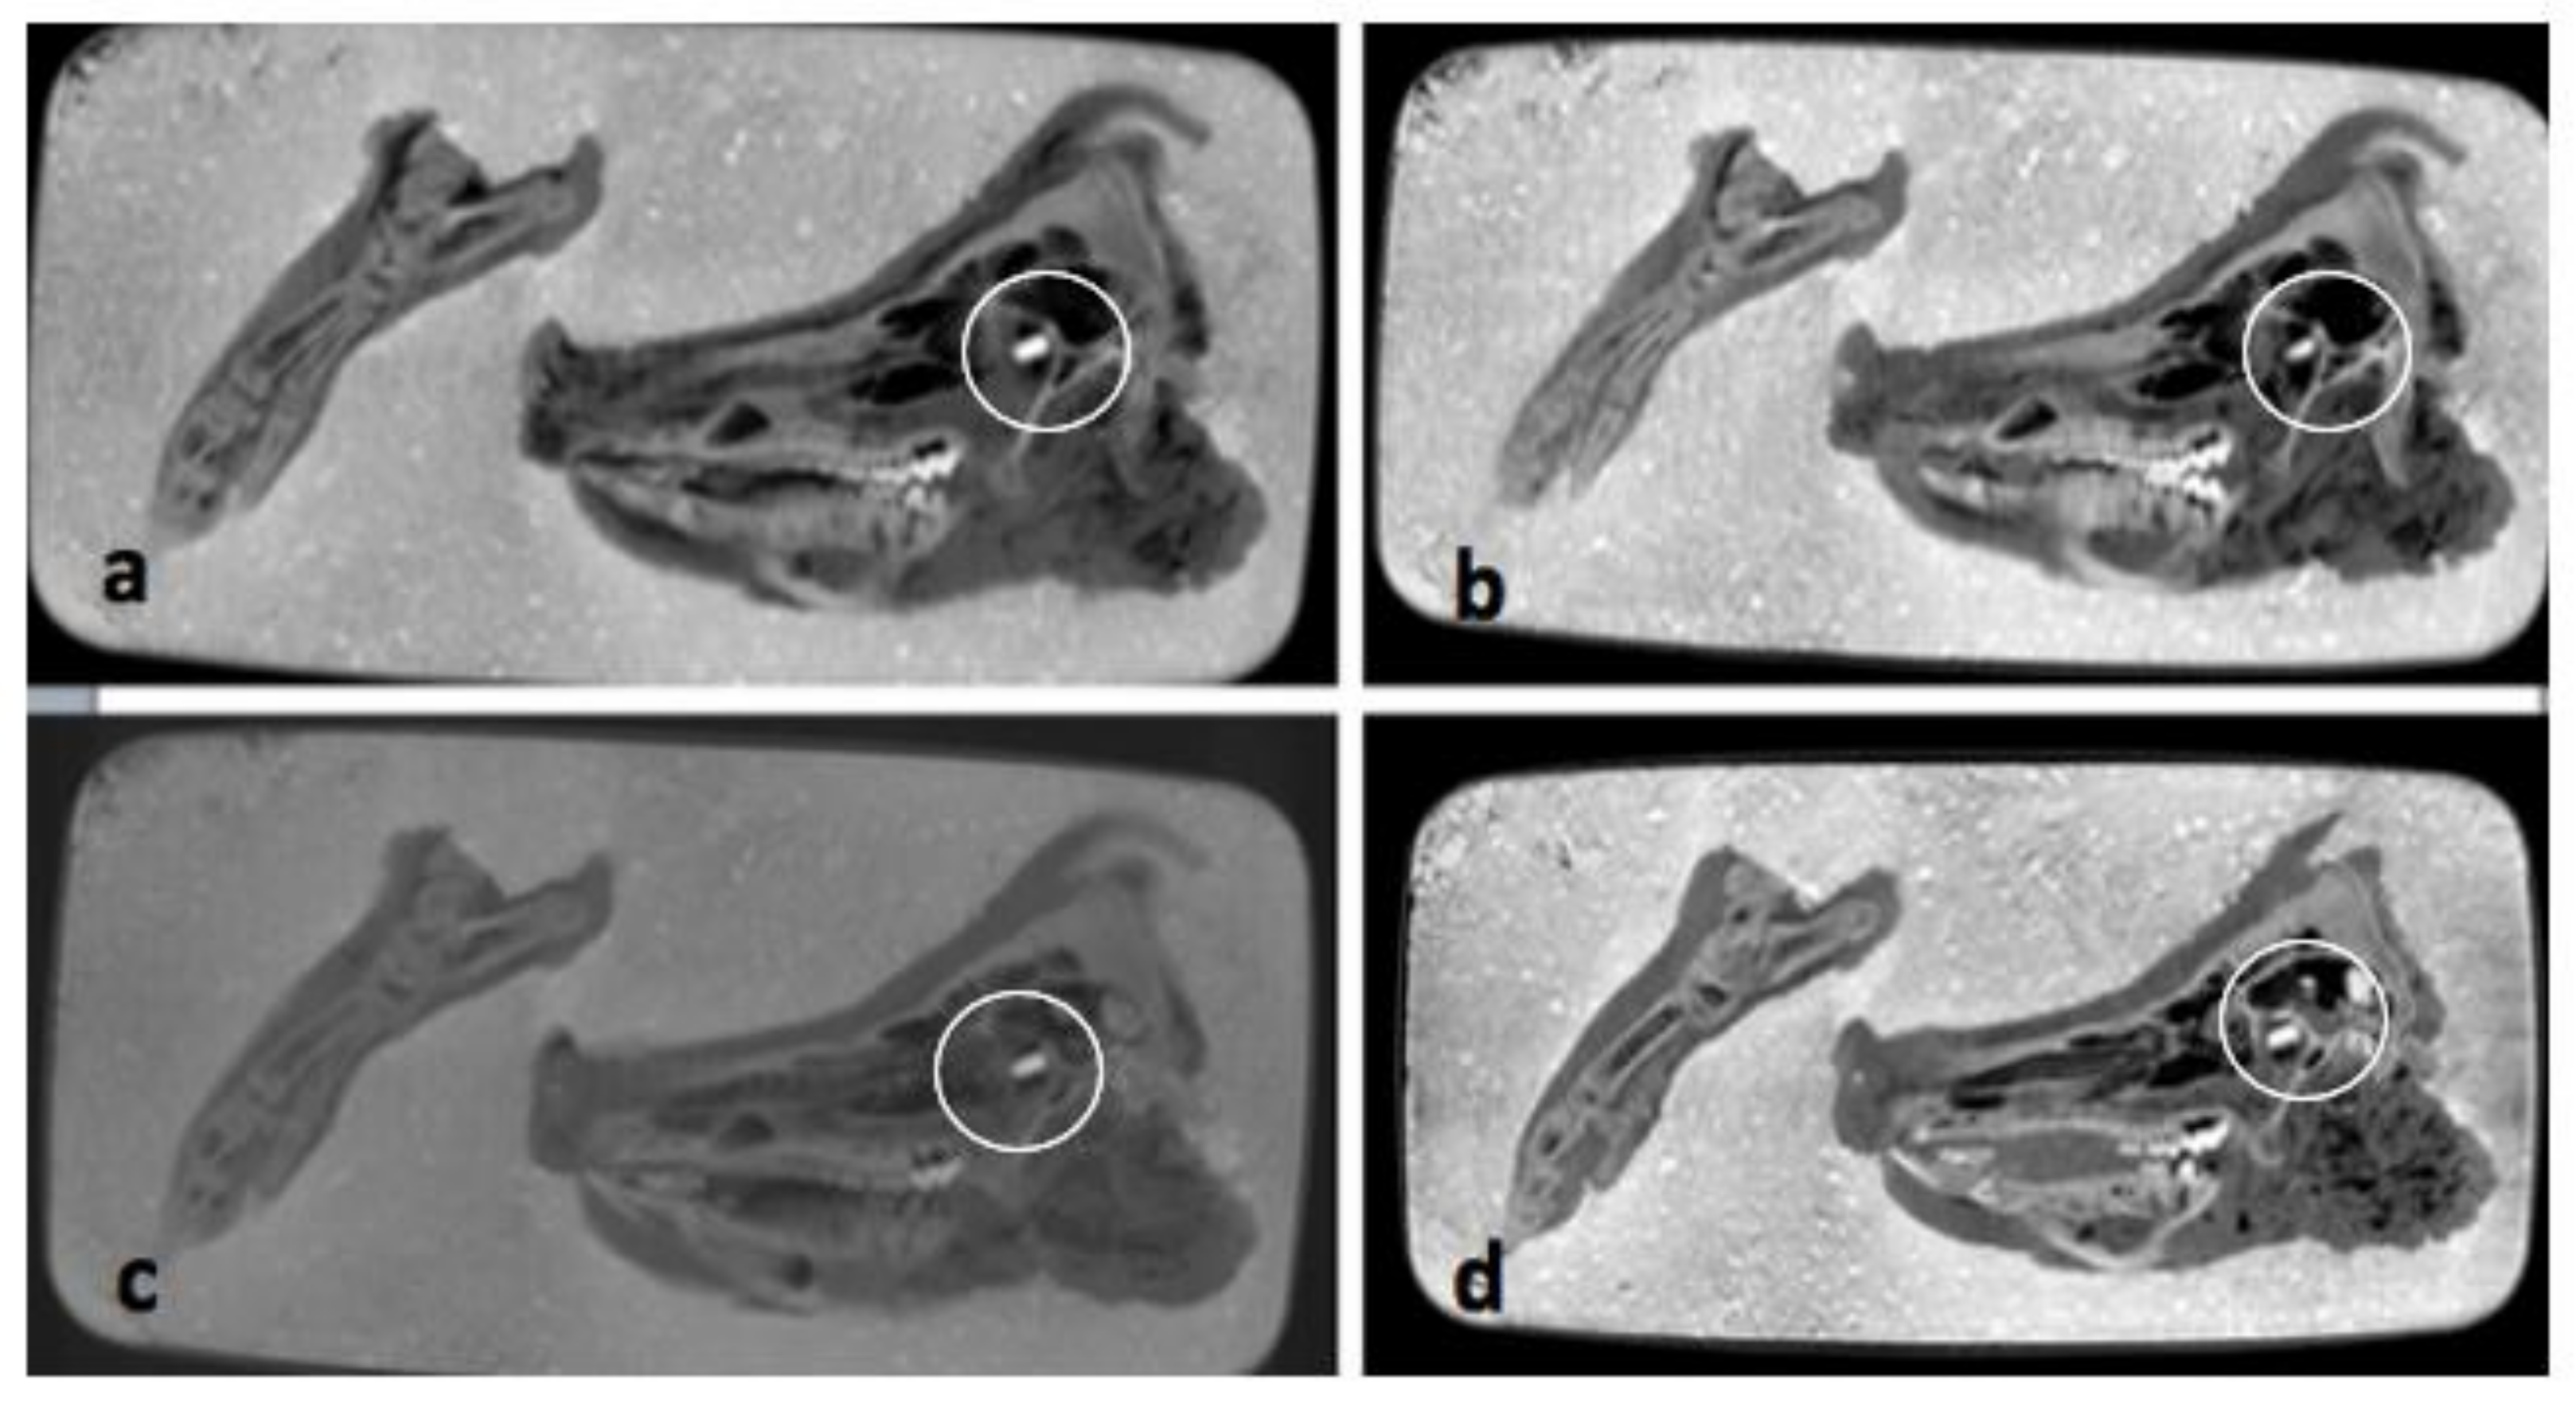

The pmCT scans in the axial plane (see Figure 4a–d), do not show any relevant changes over the course of one year. The bones and soft tissues are clearly visible on each scan, as is the projectile inside the orbit. The thickness and shape of soft tissues covering the bones remained almost unchanged over time. The amount of air inside the sinuses and soft tissues fluctuated, but there is no clear direction over time.

Figure 4.

(a–d) Comparisons of pmCT images in axial plane from 30 September 2020 (a), 21 December 2020 (b), 3 March 2021 (c) and 25 August 2021 (d). The projectile is marked with a circle in all four images.